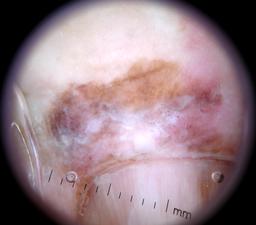

{

"age_approx": 65,

"anatom_site_general": "upper extremity",

"anatom_site_special": "acral NOS",

"concomitant_biopsy": true,

"dermoscopic_type": "non-contact polarized",

"diagnosis_1": "Malignant",

"diagnosis_2": "Malignant melanocytic proliferations (Melanoma)",

"diagnosis_3": "Melanoma in situ",

"diagnosis_confirm_type": "histopathology",

"family_hx_mm": false,

"image_type": "dermoscopic",

"mel_thick_mm": "0.00",

"melanocytic": true,

"patient_id": "IP_3069248",

"personal_hx_mm": false,

"sex": "male"